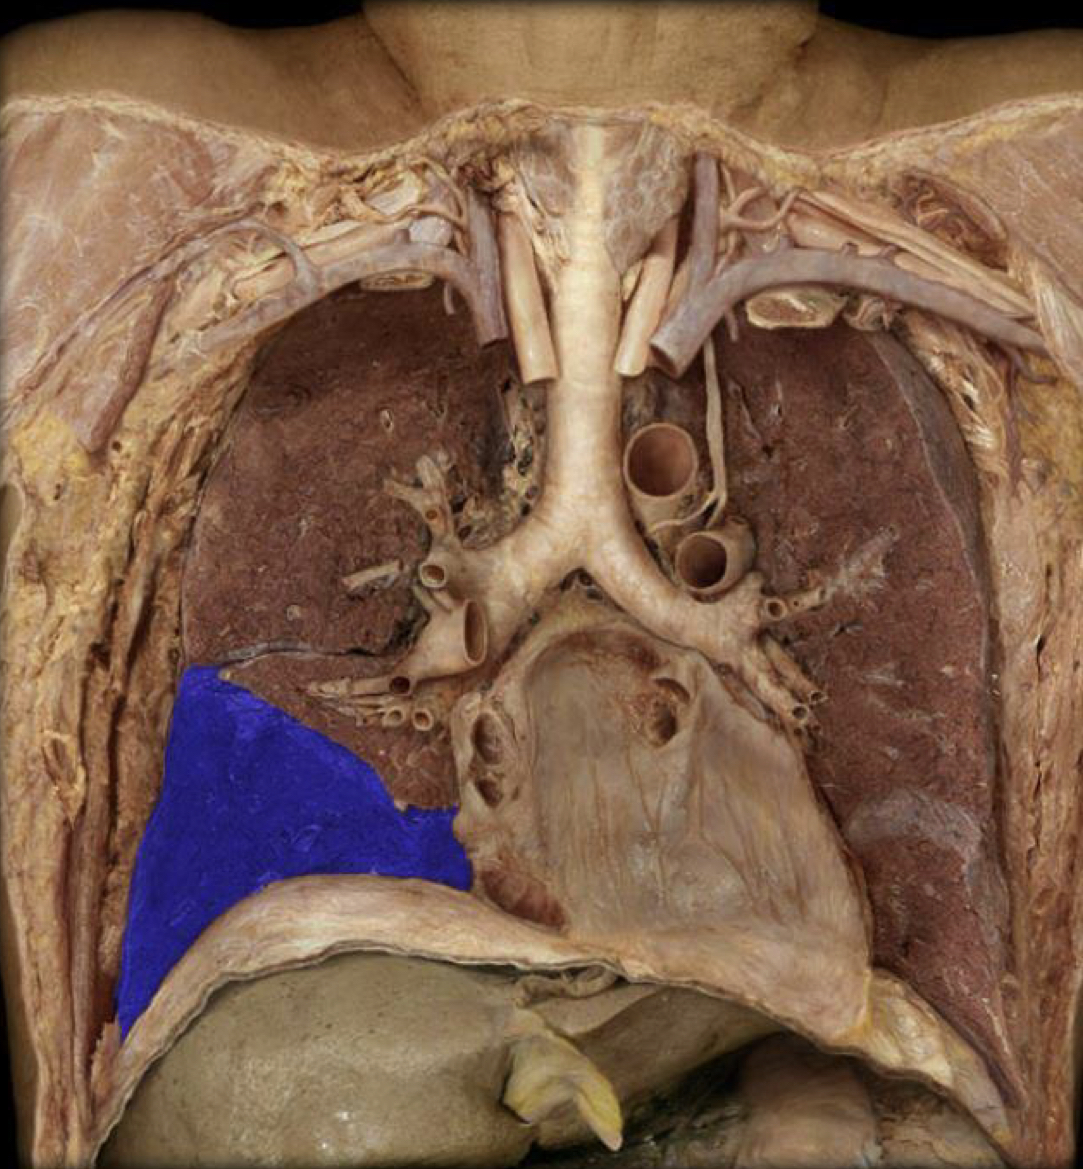

What structure is highlighted in blue?

Cardiac notch

Trachea (lower respiratory)

Right lung

Left lung

Which letter is the Pericardial sac?

B

Which letter is the Pericardial sac through mediastinal pleura?

A